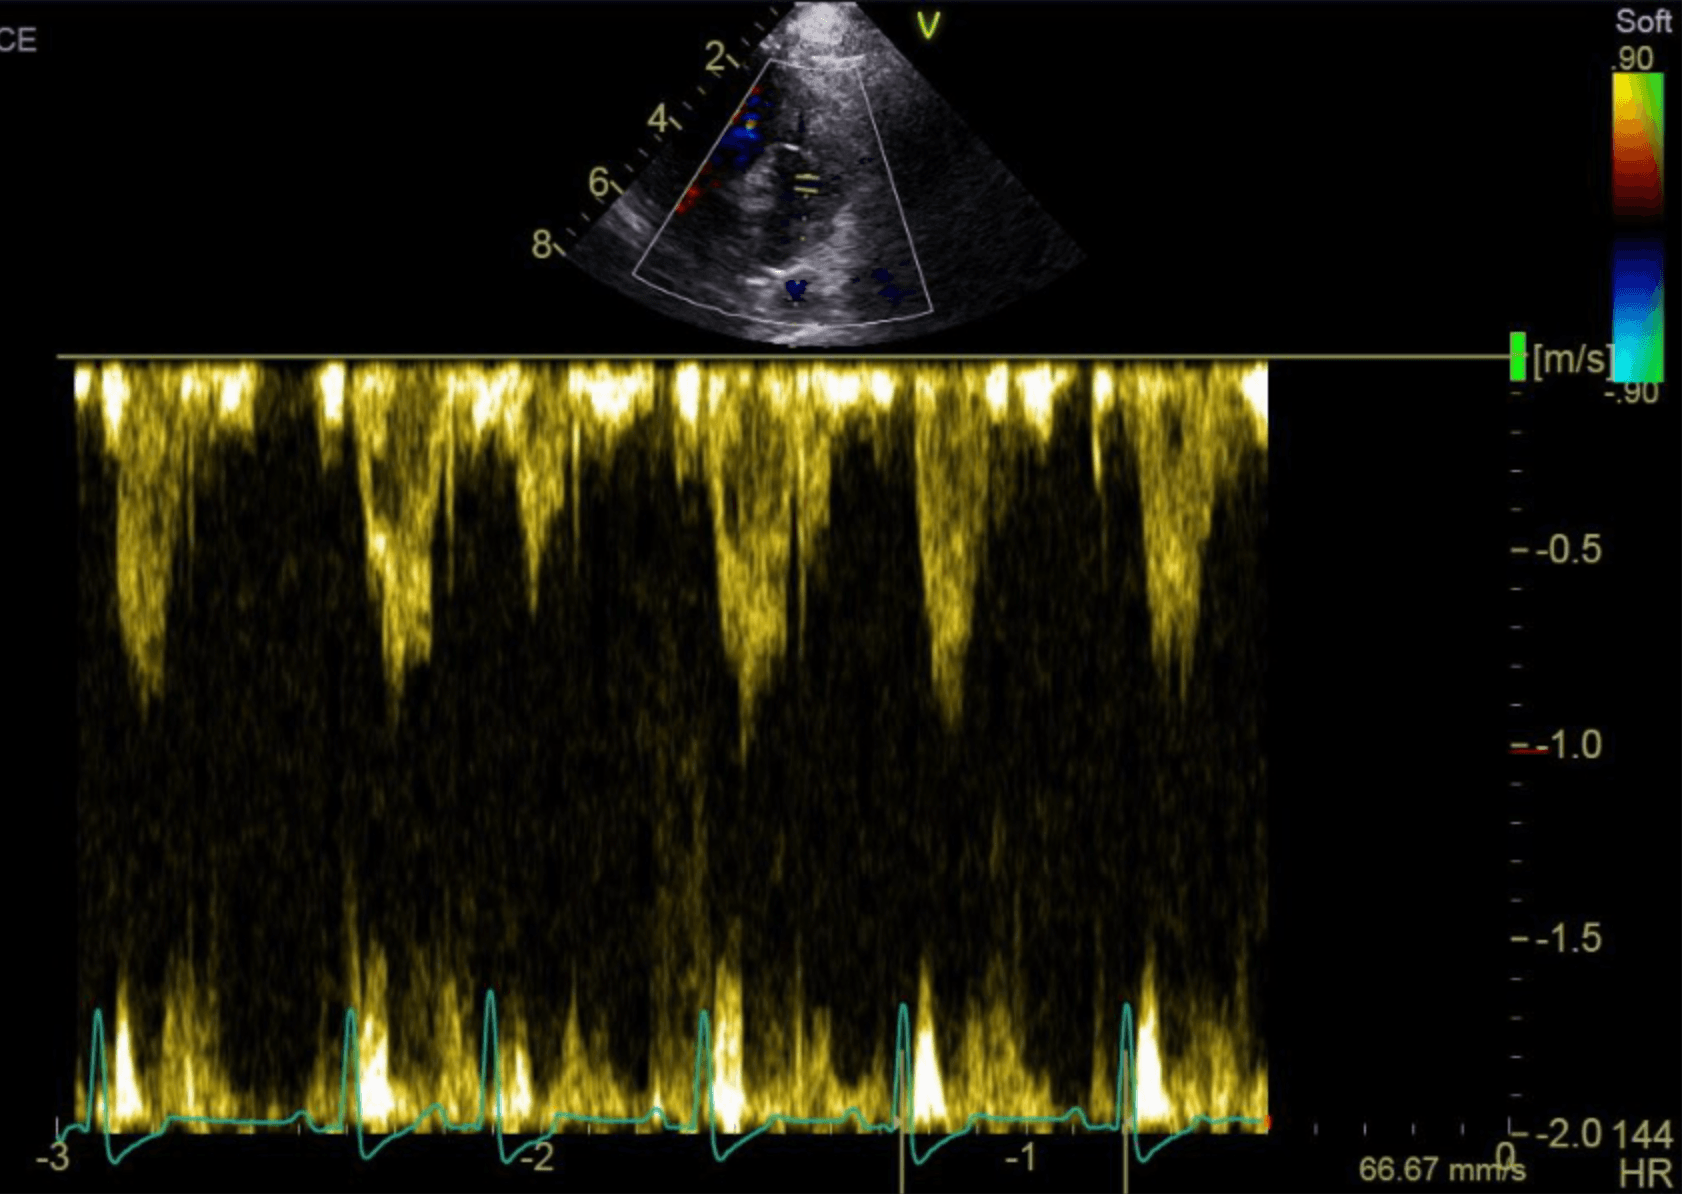

Premature atrial complexes in a Cavalier King Charles Spaniel with myxomatous mitral valve disease (stage B1).